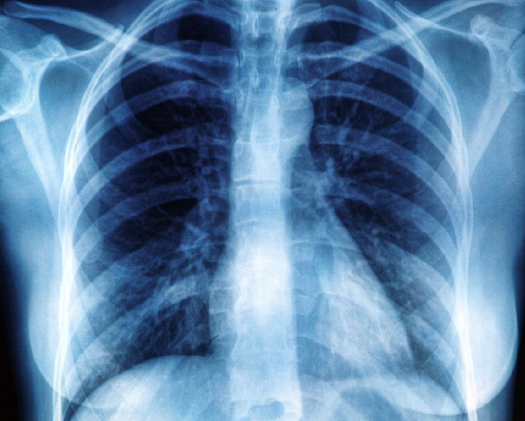

Uma situação inusitada e preocupante chamou atenção nas redes sociais, após um exame identificar um objeto estranho no ânus de um homem, que teria procurado atendimento médico, após três dias de prisão de ventre, inchaço abdominal e fortes dores.

Raio-X identificou objeto estranho em corpo de homem por Reprodução

De acordo com a equipe que o atendeu, um exame de raio-X revelou que havia uma xícara de cerâmica alojada dentro do intestino do paciente, que não conseguia evacuar. O homem foi atendido no Hospital Geral Dajia Li, em Taichung, Taiwan.

A peça, com cerca de 6 centímetros de largura e 8 de altura, tinha a superfície lisa, o que dificultou as primeiras tentativas de remoção. Médicos ainda usaram instrumentos específicos para tentar puxá-la, mas não tiveram sucesso.

De acordo com a imprensa local, o médico relatou que o paciente ficou constrangido com a situação e evitou explicar como o objeto foi parar na região. “Inacreditável, até eu fiquei chocado quando vi”, afirmou Dr. Wu Kunda.

O homem teria declarado que “não sabia” e que “foi um acidente”. Ele ainda admitiu ter tentado expulsar o objeto por conta própria antes de buscar ajuda. Com parte do intestino com sinais de comprometimento do fluxo sanguíneo, a equipe concluiu que a única saída seria recorrer a uma cirurgia de emergência sob anestesia geral. O procedimento durou cerca de duas horas.

O Dr. Wu e sua equipe abriram o abdômen do paciente, retiraram a xícara e realizaram uma colostomia temporária para permitir que ele conseguisse evacuar durante a recuperação.